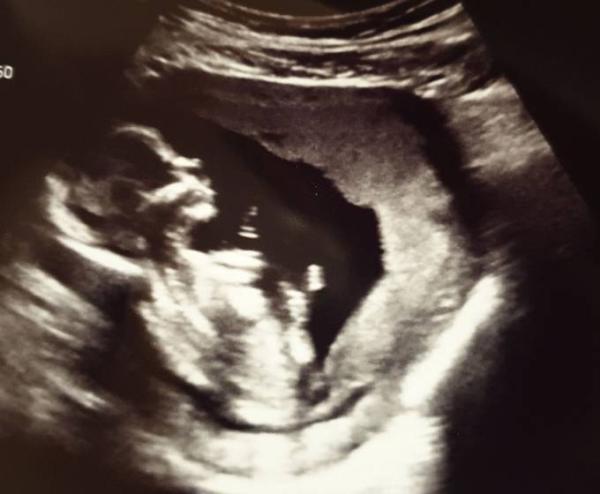

Hallo ihr Lieben Gestern war ich wieder beim Frauenarzt und unser Murkelchen ist 8,5cm groß bei 14+0. Die Beine waren aber schön zusammengekniffen Also werden wir uns wohl noch 4 Wochen gedulden müssen um das Geschlecht zu erfahren, oder vielleicht noch länger Bei unserer Tochter damals haben wir erst in der 23.ssw erfahren, dass sie eindeutig ein Mädchen ist. Aber egal was es wird, wir freuen uns riesig auf ein gesundes Murkelchen Liebe Grüße zu euch!

Bild zu Gestern endlich wieder FA Termin gehabt :) - Forum für Januar - Mamis

Ein wunderbares Bild!!! Schön, dass alles gut ist!